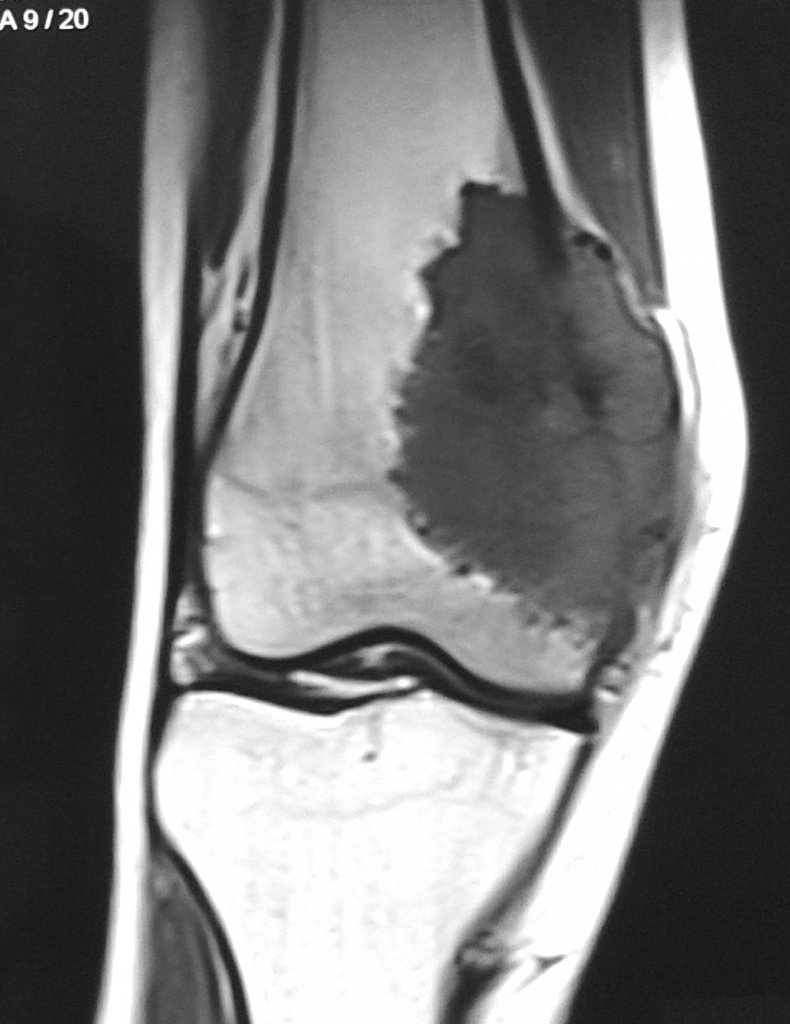

Остеосаркома коленного сустава: информация и поддержка

Раздел: Необычные решения